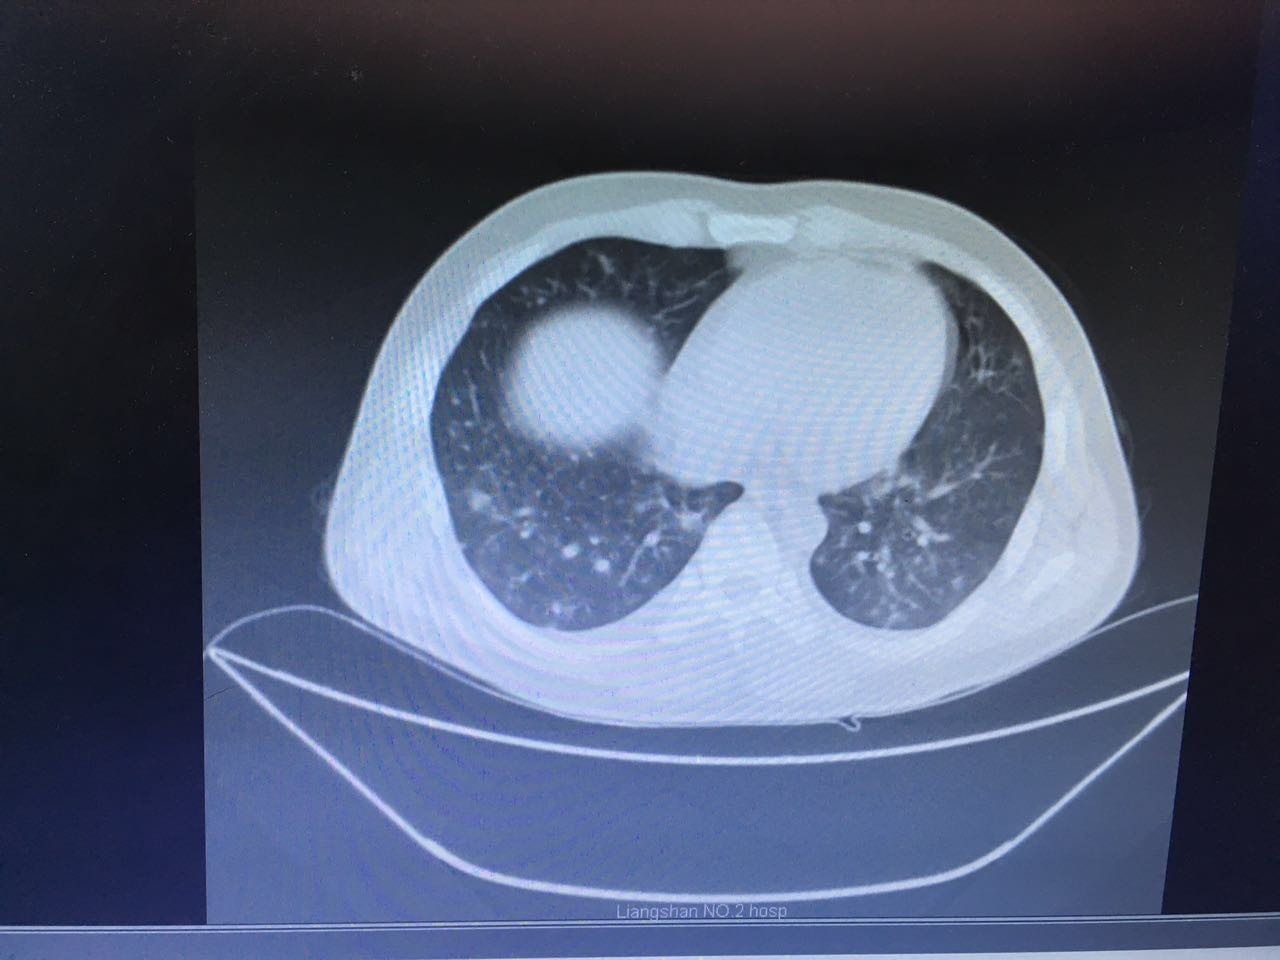

第二天,肺部CT做下来,我们傻了,和胸片差别太大了!从中下肺开始,那是大片的阴影啊!CT提示为间质性肺炎,找放射科主任读片,认为不符合肺结核、肺癌的表现(图1-3.)马上再回到病床前再次确认——没有吸烟史、没有慢性咳嗽史、没有咯血、没有盗汗史。再查体:浅表淋巴结确实不肿大,双肺呼吸音可以算略粗糙也可以算清晰。——这么这么静默的肺部体征,这么这么差的影像学结果,马上补查肿瘤标志物和自身免疫全套吧!

图3